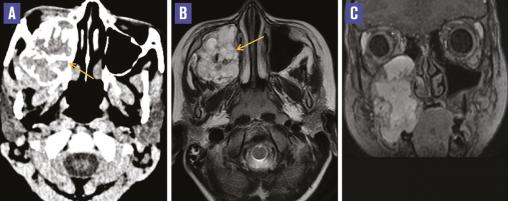

Cet enfant de 7 ans consultait pour une tuméfaction gingivale droite évoluant depuis 2 mois sans altération de l’état général. L’examen clinique notait une masse gingivale droite occupant la région maxillaire, dure, fixée avec saignement en regard (fig. 1 ). L’imagerie par résonance magnétique montrait une masse polycyclique, multiloculée, hypervasculaire, centrée sur le sinus maxillaire droit, en hyposignal T1, signal hétérogène T2, sans restriction de la diffusion, avec rehaussement intense, renfermant des zones vides de signal (fig. 2 ). La tomodensitométrie montrait cette même masse richement vascularisée, avec une composante calcifiée (fig. 2 ). L’examen histologique de la biopsie était en faveur d’un botryomycome. L’imagerie de contrôle avant le geste d’excision chirurgicale montrait une majoration en taille de la masse, renfermant des zones hématiques, responsable d’une exophtalmie homolatérale (fig. 3 ).

Le botryomycome, ou hémangiome capillaire lobulaire, est une tumeur bénigne d’origine vasculaire fréquente du tissu cutané. Les atteintes muqueuses, plus rares, concernent exceptionnellement les cavités nasosinusiennes. C’est une affection typique de l’enfance.1 Le botryomycome sinusien est trompeur et son diagnostic peut être difficile. Il peut mimer la malignité du fait de son aspect hémorragique charnu, unilatéral et ulcéré et de sa croissance rapide. Il n’y a pas d’aspect spécifique sur l’imagerie. L’extension et la base d’implantation peuvent être visualisées par la TDM et l’IRM.2 Le diagnostic est histologique. Le caractère récidivant impose une exérèse complète. La biopsie et l’excision totale doivent de préférence être effectuées en une seule étape, au bloc opératoire sous anesthésie générale, pour éviter une hémorragie secondaire. Une excision incomplète peut fausser le diagnostic anatomopathologique si l’échantillon ne comporte pas d’ulcération muqueuse.